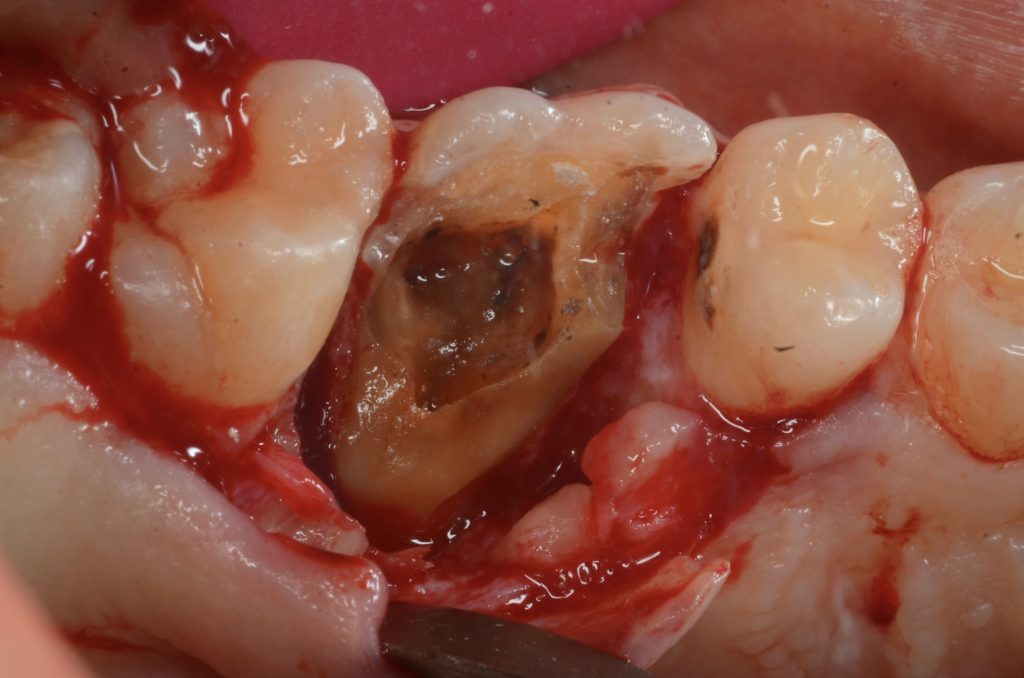

في الزيارة الثانية لاحظنا كسر بصري في جدار الحنك (المريض في ذلك الوقت كان يعاني من الإجهاد ونير الأسنان أثناء النوم)

After first visit horizontal fracture occurred

Remove piece of fracture

Crown lengthing procedure